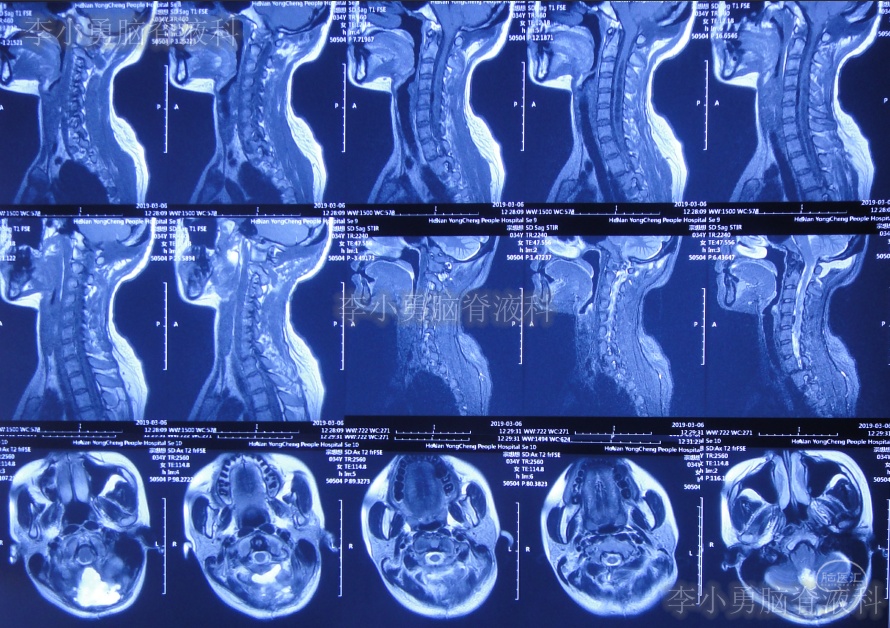

患者2019年2月初,因数次出现发作性黑蒙,2019年2月10日就诊于当地的河南省永城市某医院,查头颅CT未见明显异常(图-1);次日再查头颅核磁、颈椎核磁(图-2、图-3)后发现小脑扁桃体下疝畸形合并脊髓空洞。

图-1:2019年2月10日头颅CT

图-2:2019年2月12日头颅核磁

图-3:2019年2月13日头颅核磁

小脑扁桃体下疝减压术后20天即2019年3月6日,查头颅、颈椎核磁发现仍有脊髓空洞(图-8、图-9)。

图-8:2019年3月6日头颅核磁

图-9:2019年3月6日头颅核磁